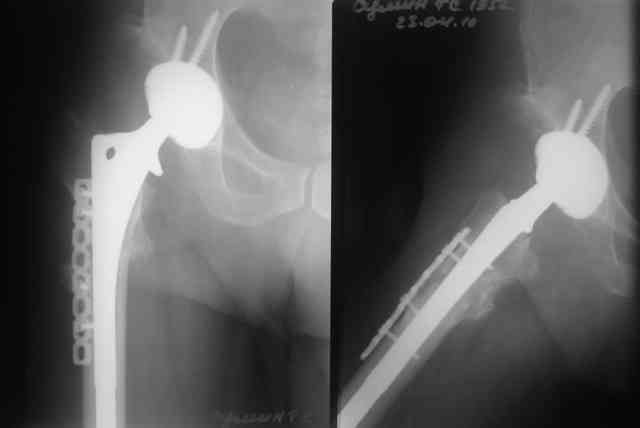

Был у нас подобный случай

Выполнена одномоментная коррекция деформации, эндопротезирование DePyu Pinnacle-AML. Пластинка с деротационной целью. При использовании ножки с прямоугольным сечением, думаю, можно и без нее.

В прищепке случай 1999 года - эндопротезирование после операции Шанца-Илизарова. Возраст пациентки 45. Коррекция была в 17 лет. А Рыков Хабаровск.